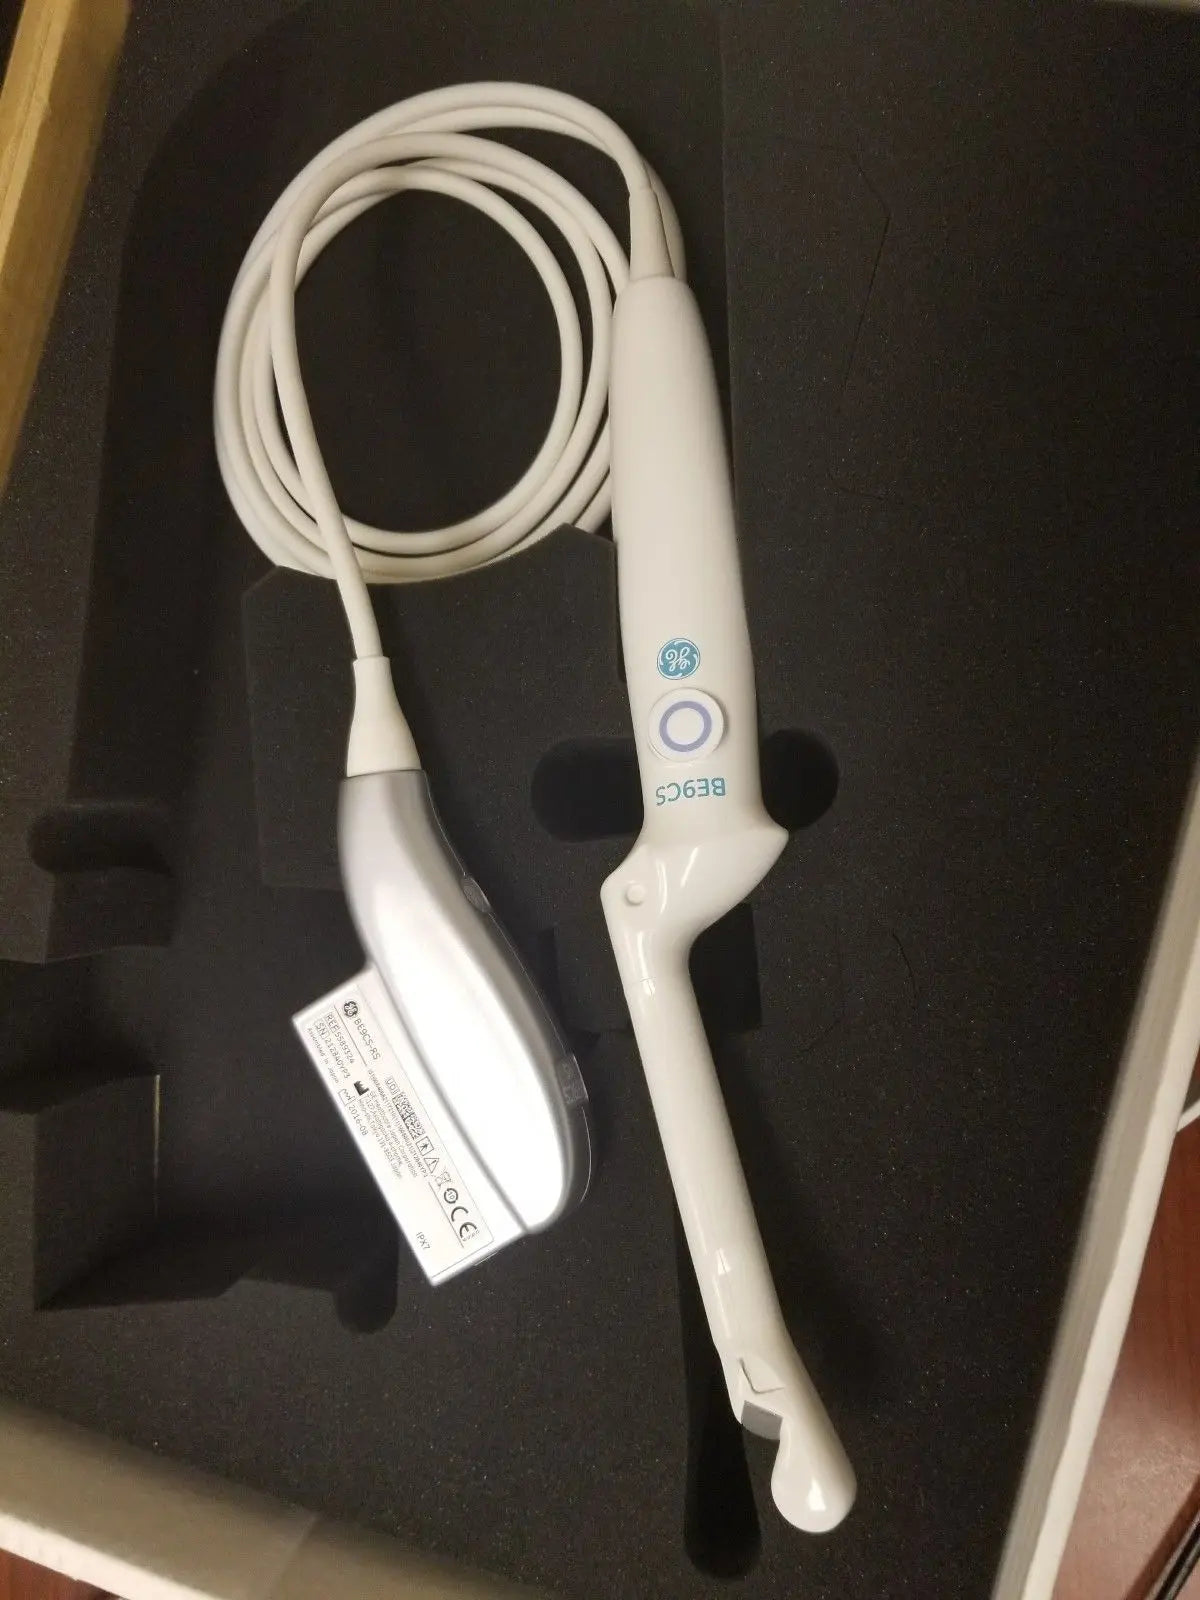

DIAGNOSTIC ULTRASOUND MACHINES FOR SALE

2017 GE IC9 -RS probe for GE Ultrasound

Sale price$ 8,395.14